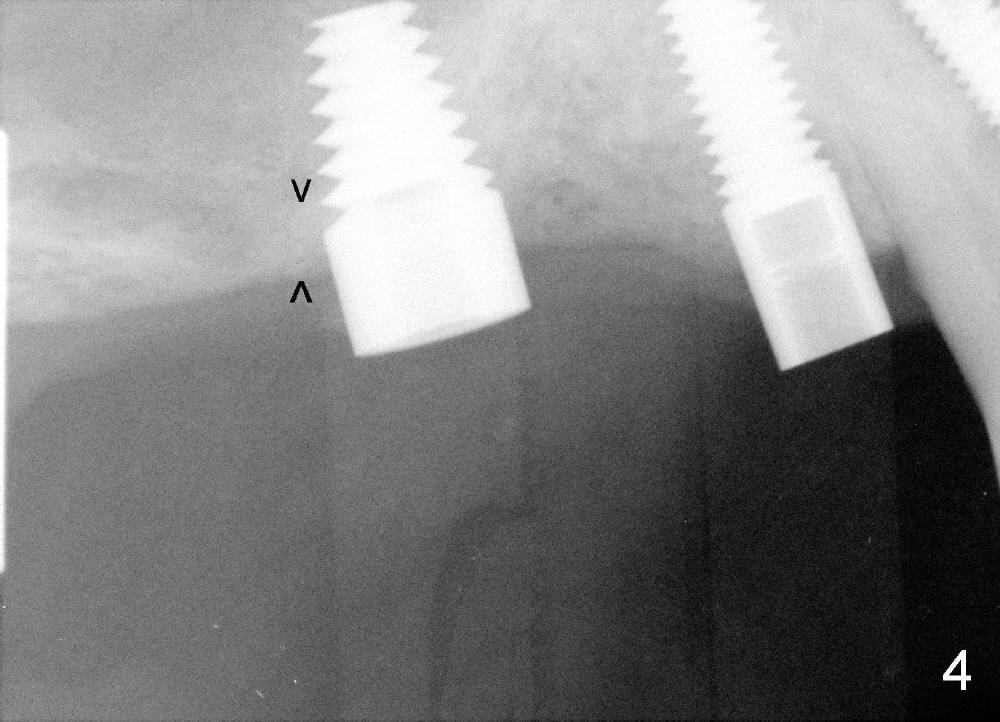

It appears that sinus graft is necessary for #3-5 implant placement (Fig.1). Mr. Wu says "Do whatever you think appropriate." But the framework partial denture is suddenly broken at the major connector. He cannot eat well. We do not have time to do sinus graft! Short implant is planned to be placed at the site of #3 (5x11 mm, Fig.1). After initial bone expansion until RT 2 mm (as mentioned above), two-mm pilot drills are inserted at the sites of #3 and 5 (Fig.2). The sinus floor is perforated at #3. The osteotomy for #3 is then moved mesially ~ 2 mm using osteotomes (RT 2-4mm). While bone expansion (osteotomes and taps) is being used to create osteotomy for #3, tapered drills for #5. Fig.3 shows 5x11 mm tap and 3.5x20 mm drill in place. Finally 6x11 mm and 4x20 mm implants are placed with >60 Ncm (Fig.4). The patient is also doing great nearly two weeks postop. A third implant is planned to be placed at the site of #5 1-3 months later.